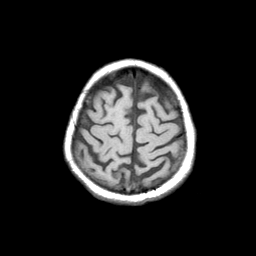

Basal Ganglia Calcification: T1-weighted MR -- Slice #15

[Home][Help][Clinical] Slice 15